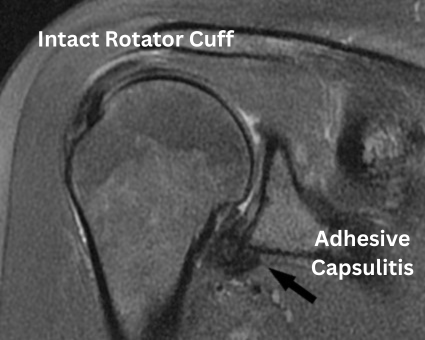

If you found your way to this book, you probably have had symptoms for many days or weeks already, as the unexplained onset of pain with frozen shoulder (FS) can be quite baffling for a while until you eventually find out about this mysterious affliction. There are many other possible causes of shoulder pain, but when you start to lose your range of motion (ROM) it inevitably leads you down the adhesive capsulitis rabbit hole on a quest for answers. For more details about the book see the Frozen Shoulder Healing blog.